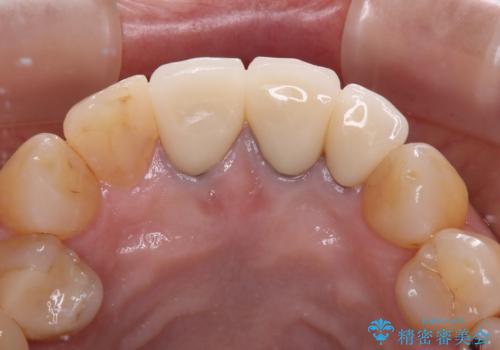

透明感のある自然な色合いとなり、患者様には大変満足していただけました。